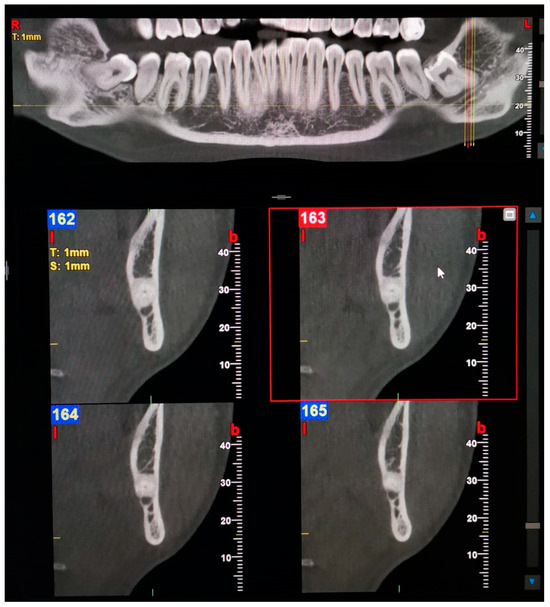

Examples of images considered positive for BMC and TMC are shown in Figure 1, Figure 2, Figure 3, Figure 4, Figure 5, Figure 6 and Figure 7. Regarding the distribution among patients, 36 subjects (15.13%) showed at least one BMC, 12 (5.04%) bilaterally, while 2 subjects (0.84%) showed a TMC. Among patients with cases considered positive for BMC, 21 were women, accounting for 8.82% of the total studied population and 14.89% of female patients overall. On the other hand, 15 BMC patients were men, accounting for 6.30% of the whole sample and 15.4% of men in the study. Considering the hemi-mandibles, BMC appeared in 9.87% of images, while TMC only appeared in 0.42%. The Patient group that was positive for BMCs had a mean age of 34 ± 13.30, while the group that was positive for TMCs presented a mean age of 43 ± 19.8. Pearson’s Chi-Square test was not significant; no association was found between gender and the prevalence of mandibular canals.

Figure 3. Panoramic view and transverse section of a left Type 3—Forward BMC with confluence. l, lingual. b, buccal. T, thickness. S, section.